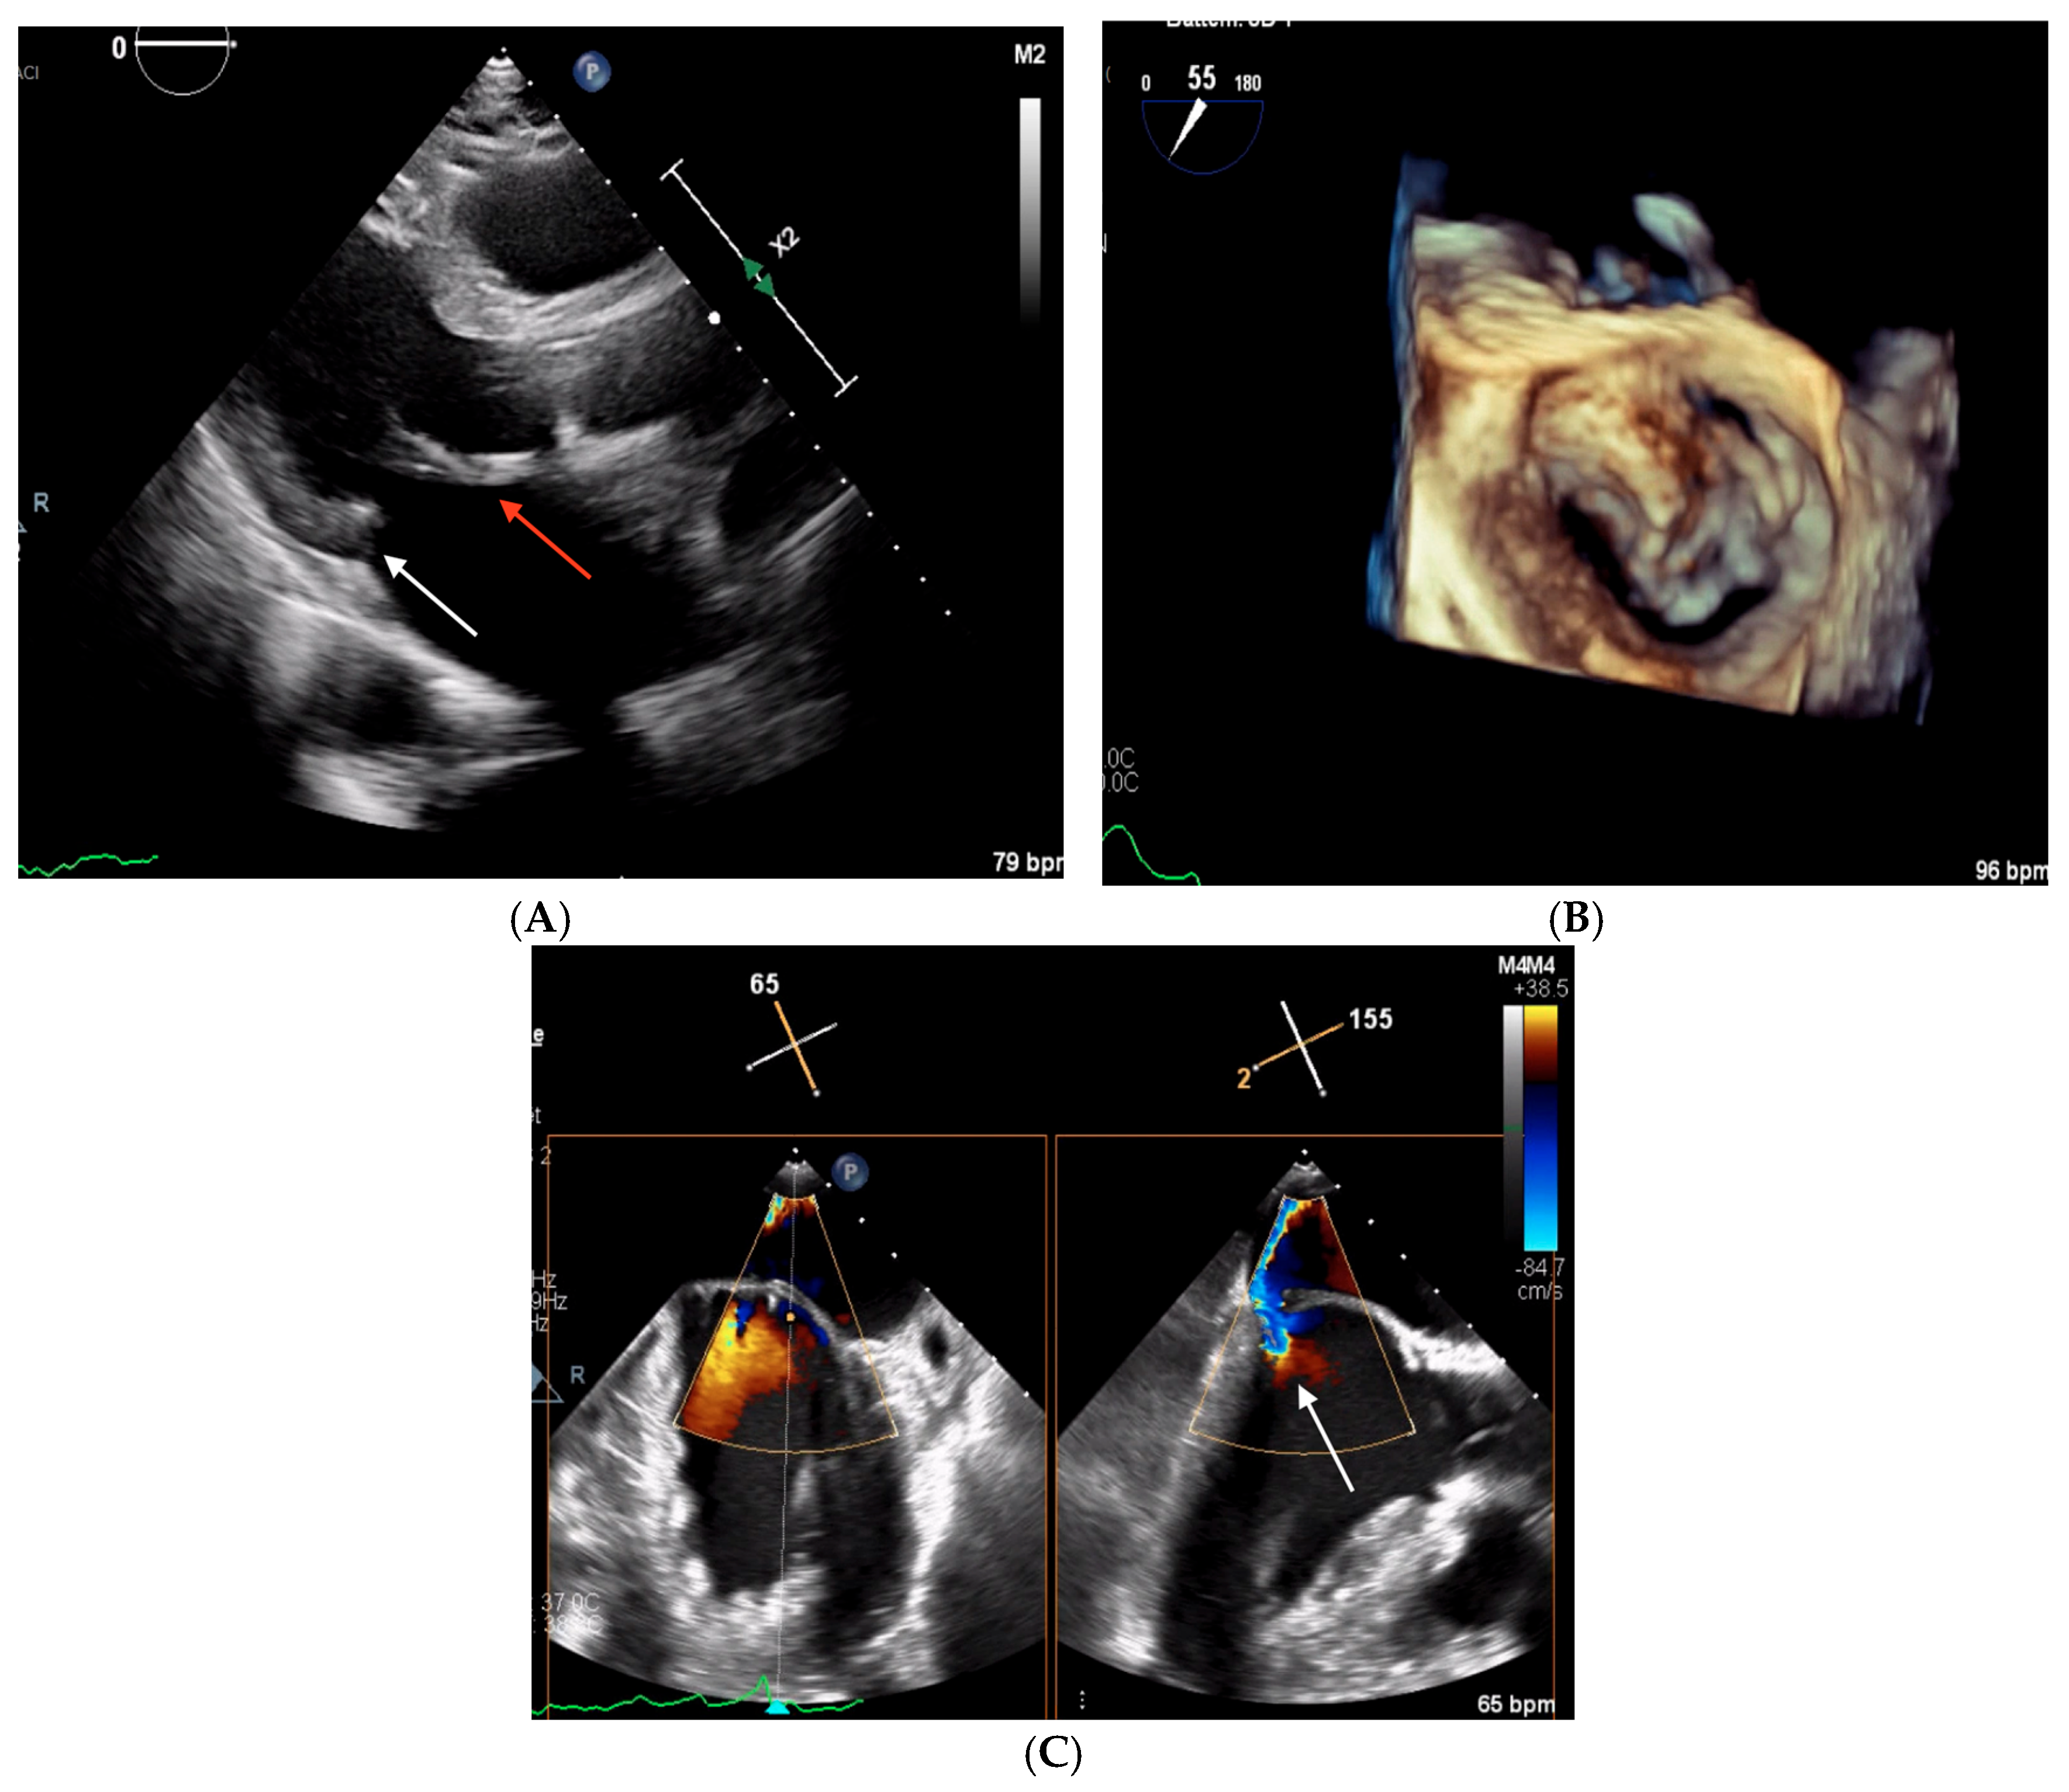

2.3. Clinical Case 3